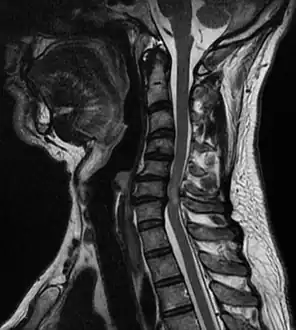

Compressive myelopathy at the C6-C7 level due to disc protrussion